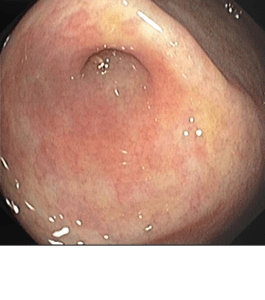

La reconstrucción virtual es una técnica avanzada en radiología diagnóstica que aprovecha la tecnología de tomografía computarizada (TC) para crear representaciones detalladas y precisas del cuerpo humano en tres dimensiones. Este proceso transforma las imágenes obtenidas por el escáner TC en modelos tridimensionales que reflejan fielmente la anatomía y estructuras internas del paciente.

- Diagnóstico Preciso: La reconstrucción virtual permite a los médicos visualizar con precisión estructuras anatómicas complejas, detectar anomalías, evaluar la extensión de lesiones o enfermedades, y realizar diagnósticos más precisos.

- Educación y Formación: Los modelos tridimensionales generados por la reconstrucción virtual son también herramientas educativas poderosas para estudiantes de medicina y para la formación de profesionales médicos en prácticas quirúrgicas y procedimientos intervencionistas.